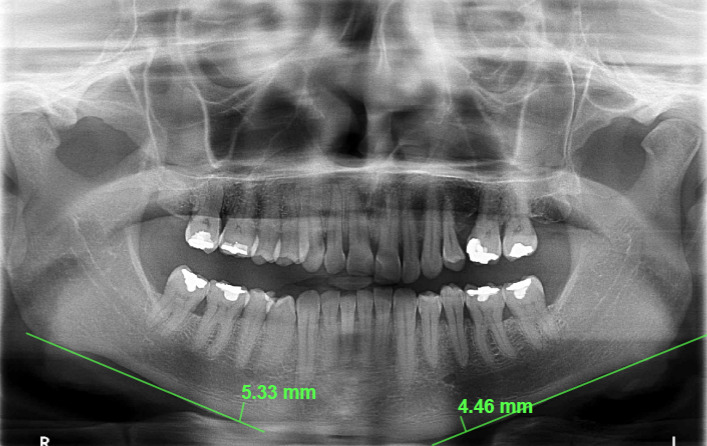

For the Mandibular Cortical Index, three classifications were considered: C1 (the endosteal margin of the mandibular cortex appeared visibly smooth), C2 (the endosteal margin exhibited semilunar defects or lacunar resorption), and C3 (the cortical bone showed evident endosteal residues and appeared porous) (Figure 2). Additionally, the thickness of the mandibular cortices (Mental Index) on both sides was measured using Studio 3 Software (Radio Memory, Belo Horizonte, Brazil). Images were imported into the software in digital format to maintain original quality and resolution. Linear measurements were conducted using the software's calibrated virtual rulers. These measurements were taken by measuring the distance from a line drawn through the center of the mental foramen to a perpendicular line intersecting the mandibular border (Figure 3).

Figure 3: Mental Index measurement on panoramic radiograph. The measurement was made by drawing a line through the center of the mental foramen to a perpendicular line that intersected the edge of the mandible. View Figure 3